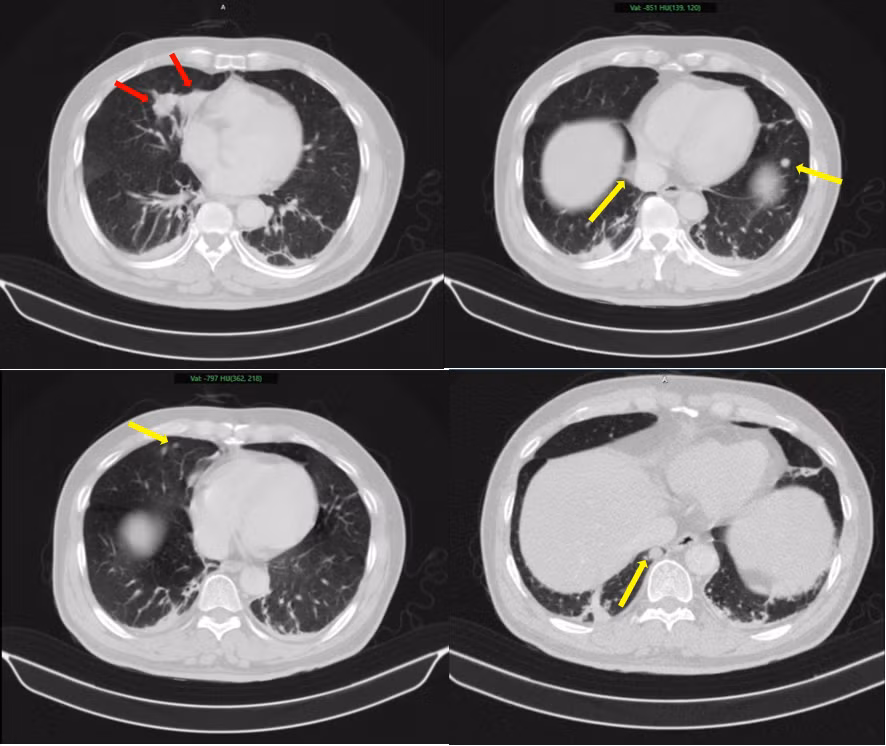

Hình ảnh 2 khối u bờ đa cung ở nhu mô thùy giữa phổi phải, dính vào màng phổi trung thất (mũi tên đỏ) kèm nhiều nốt đặc nhỏ rải rác nhu mô phổi hai bên (mũi tên vàng) gợi ý tổn thương thứ phát - Ảnh BVCC